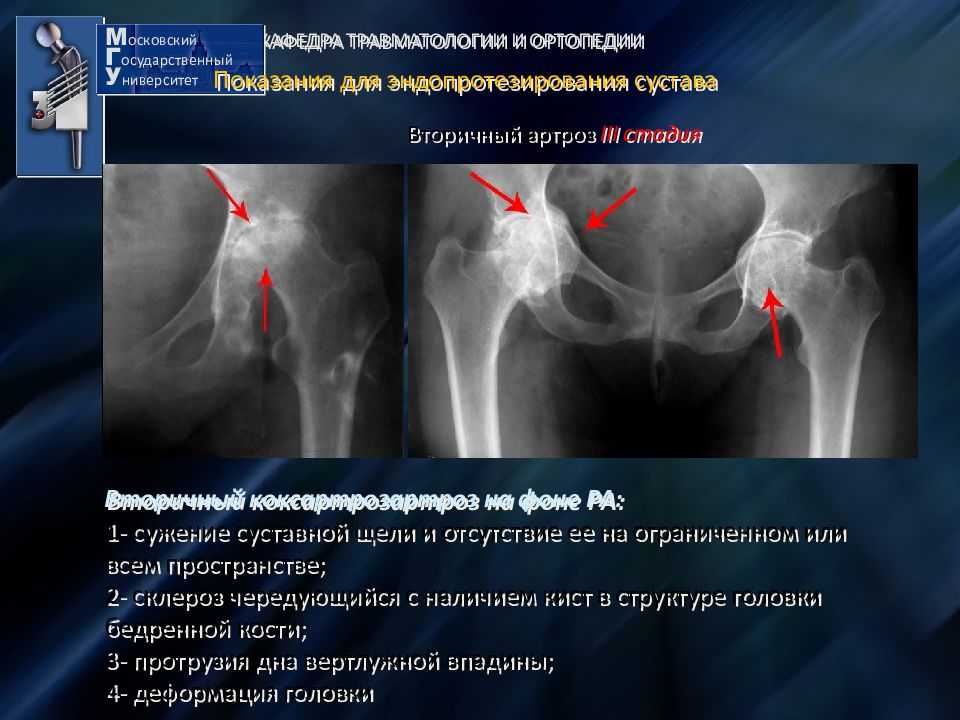

Фотографии и схемы: Коксит правого тазобедренного сустава